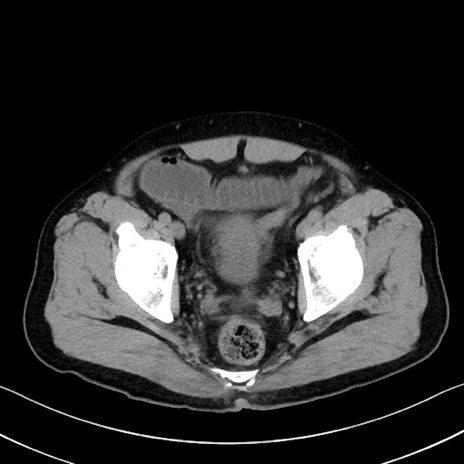

症例35(横断像)

【症例】70歳代 男性

【主訴】腹部膨満、嘔吐

【現病歴】昨日より腹部膨満感出現。本日増悪し、仙痛出現。嘔吐あり、受診。

【既往歴】糖尿病、胆摘後

【身体所見】BP 149/80mmHg、HR 74/min、BT 35.9℃、腹部:膨満、軟、圧痛なし。腸雑音減弱あり。上腹部正中切開瘢痕あり。

【データ】WBC 13500、CRP 1.72